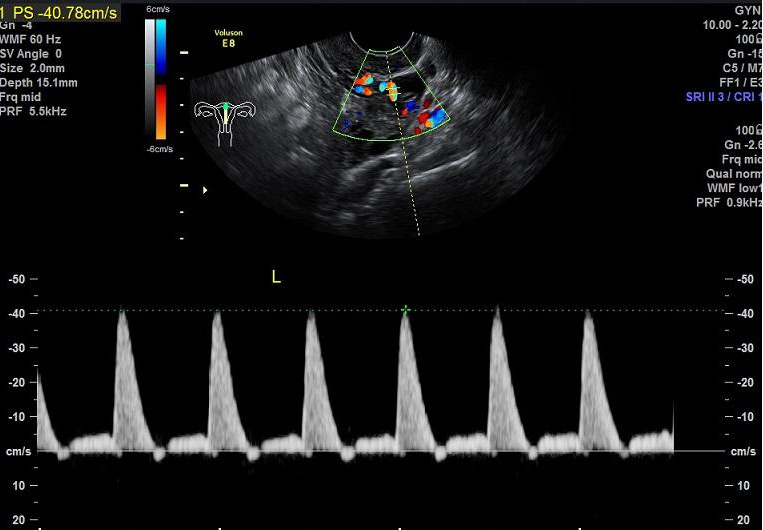

而我们通过B超可以很容易地了解到子宫动脉的血流情况。而最常见代表子宫动脉供血情况的参数包括搏动指数(PI)、阻力指数(RI)及收缩期峰值流速/舒张期流速(S/D)。

而子宫动脉血流指数在月经周期的不同时段会有所不同,正常情况下,排卵后的黄体期(受精卵着床时期)间子宫动脉的血流量增加,这对受精卵着床就非常有益。PI和RI值越低说明卵巢和子宫的血流灌注情况越好,胚胎着床率也就越高。一般来说,在妊娠前子宫动脉血流动力学参数的正常范围是RI<0.85,PI<3,双侧S/D之和<12。一旦发现子宫动脉血流动力学参数检查异常,应及时在医生指导下进行抗凝治疗、改善血流灌注。低剂量阿司匹林、肝素等可有效改善子宫动脉血流灌注,可能增加子宫内膜厚度,提高子宫内膜对胚胎的容受性,降低胚胎停止发育的风险。